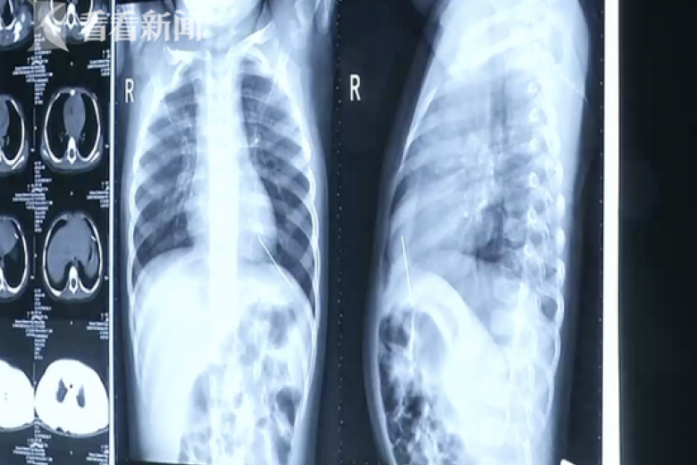

Cây kim có đường kính 2mm bị mắc kẹt trong tâm thất trái của Chenchen.

Sau khi chụp X-quang, các bác sỹ cho biết có một vật thể lạ nằm trong khoang ngực của cô bé.

Sau khi thực hiện ca phẫu thuật gắp kim thành công, cách bác sỹ cho biết cây kim có đường kính 2mm bị mắc kẹt trong tâm thất trái của đứa trẻ trong một thời gian vì nó đã bị rỉ.